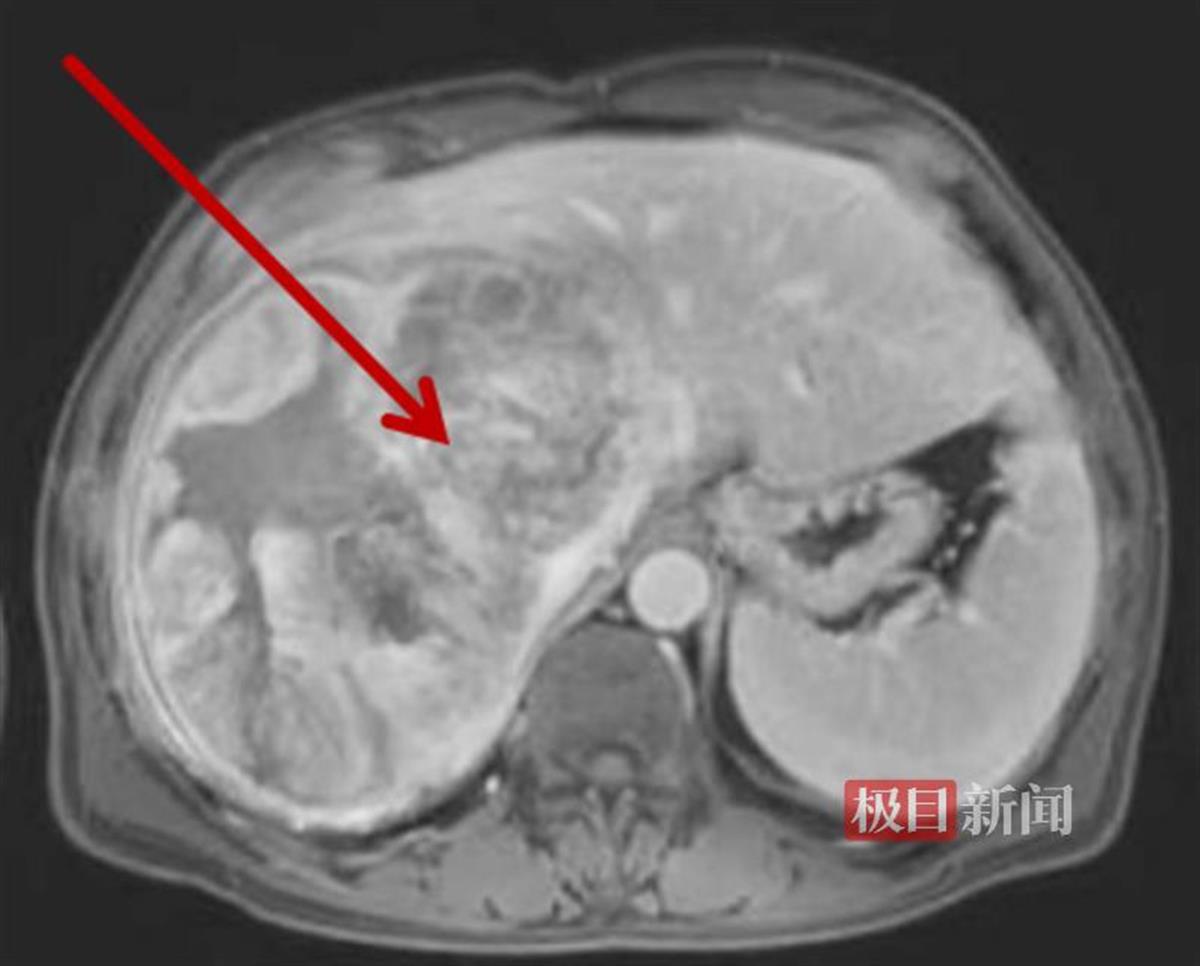

经CT检查发现,他的肝脏上长了个巨大的球形肿瘤,直径约20厘米。更凶险的是,它随时有破裂大出血的风险,必须尽快手术。考虑到疾病凶险,当地医院紧急联系后将患者转至武汉协和医院车谷院区肝胆胰外科/肝脏移植中心,并在短时间内完成术前检查。

术前影像检查发现肝脏巨大肿瘤